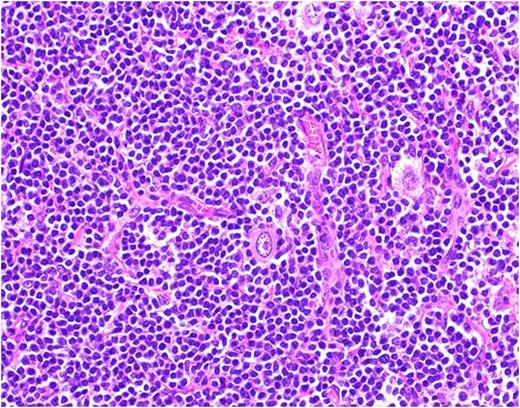

A 59 year old male with no significant medical history presented with progressive swelling and erythema of the right testis. Testicular cancer was suspected and he underwent a radical right inguinal orchiectomy. Pathology revealed a 5.7cm seminoma of the testis with lymphovascular invasion and without spermatic cord involvement (pT2) (Fig. 1). His tumor markers including AFP, LDH, and Beta-HCG were normal (S0). A CT scan of the chest, abdomen and pelvis followed by a PET/CT revealed enlarged, hypermetabolic mediastinal, hilar and periportal lymphadenopathy interpreted by the radiologist as concerning for metastatic disease. Given the atypical distribution for lymphadenopathy from testicular seminoma, an excisional biopsy of a left hilar node was performed and revealed Classical Hodgkin Lymphoma with IHC positive for CD15, CD30 and PAX-5 (Fig 2). He denied any B-symptoms and his bone marrow was uninvolved by lymphoma (stage IIIA). Adjuvant therapy for his germ cell tumor, otherwise an important consideration, was deferred and he began chemotherapy with adriamycin, bleomycin, vinblastine and dacarbazine (ABVD) for 6 cycles. Interim PET/CT after 2 cycles of ABVD showed a complete response. He has completed 6 cycles of ABVD and chose observation as opposed to single dose of adjuvant carboplatin for his seminoma and is currently under surveillance for both malignancies.

Testicular mass- Seminoma

Lymph node biopsy- Classic Hodgkin's lymphoma